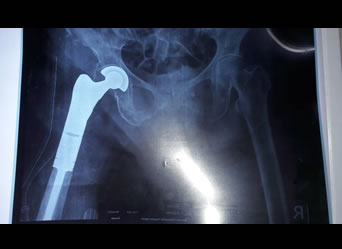

Proximal Femoral Endoprosthetic Replacement

xray of a successful Total Knee Replacement